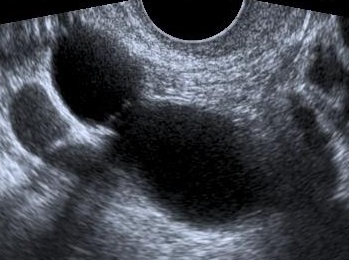

Ultrasound findings

- Frequently large, unilateral, cystic mass.

- Usually multilocular.

- Smooth walls.

- Contains small cystic components or honeycomb-like loculi.

- Intralocular fluid of varying echogenicity.